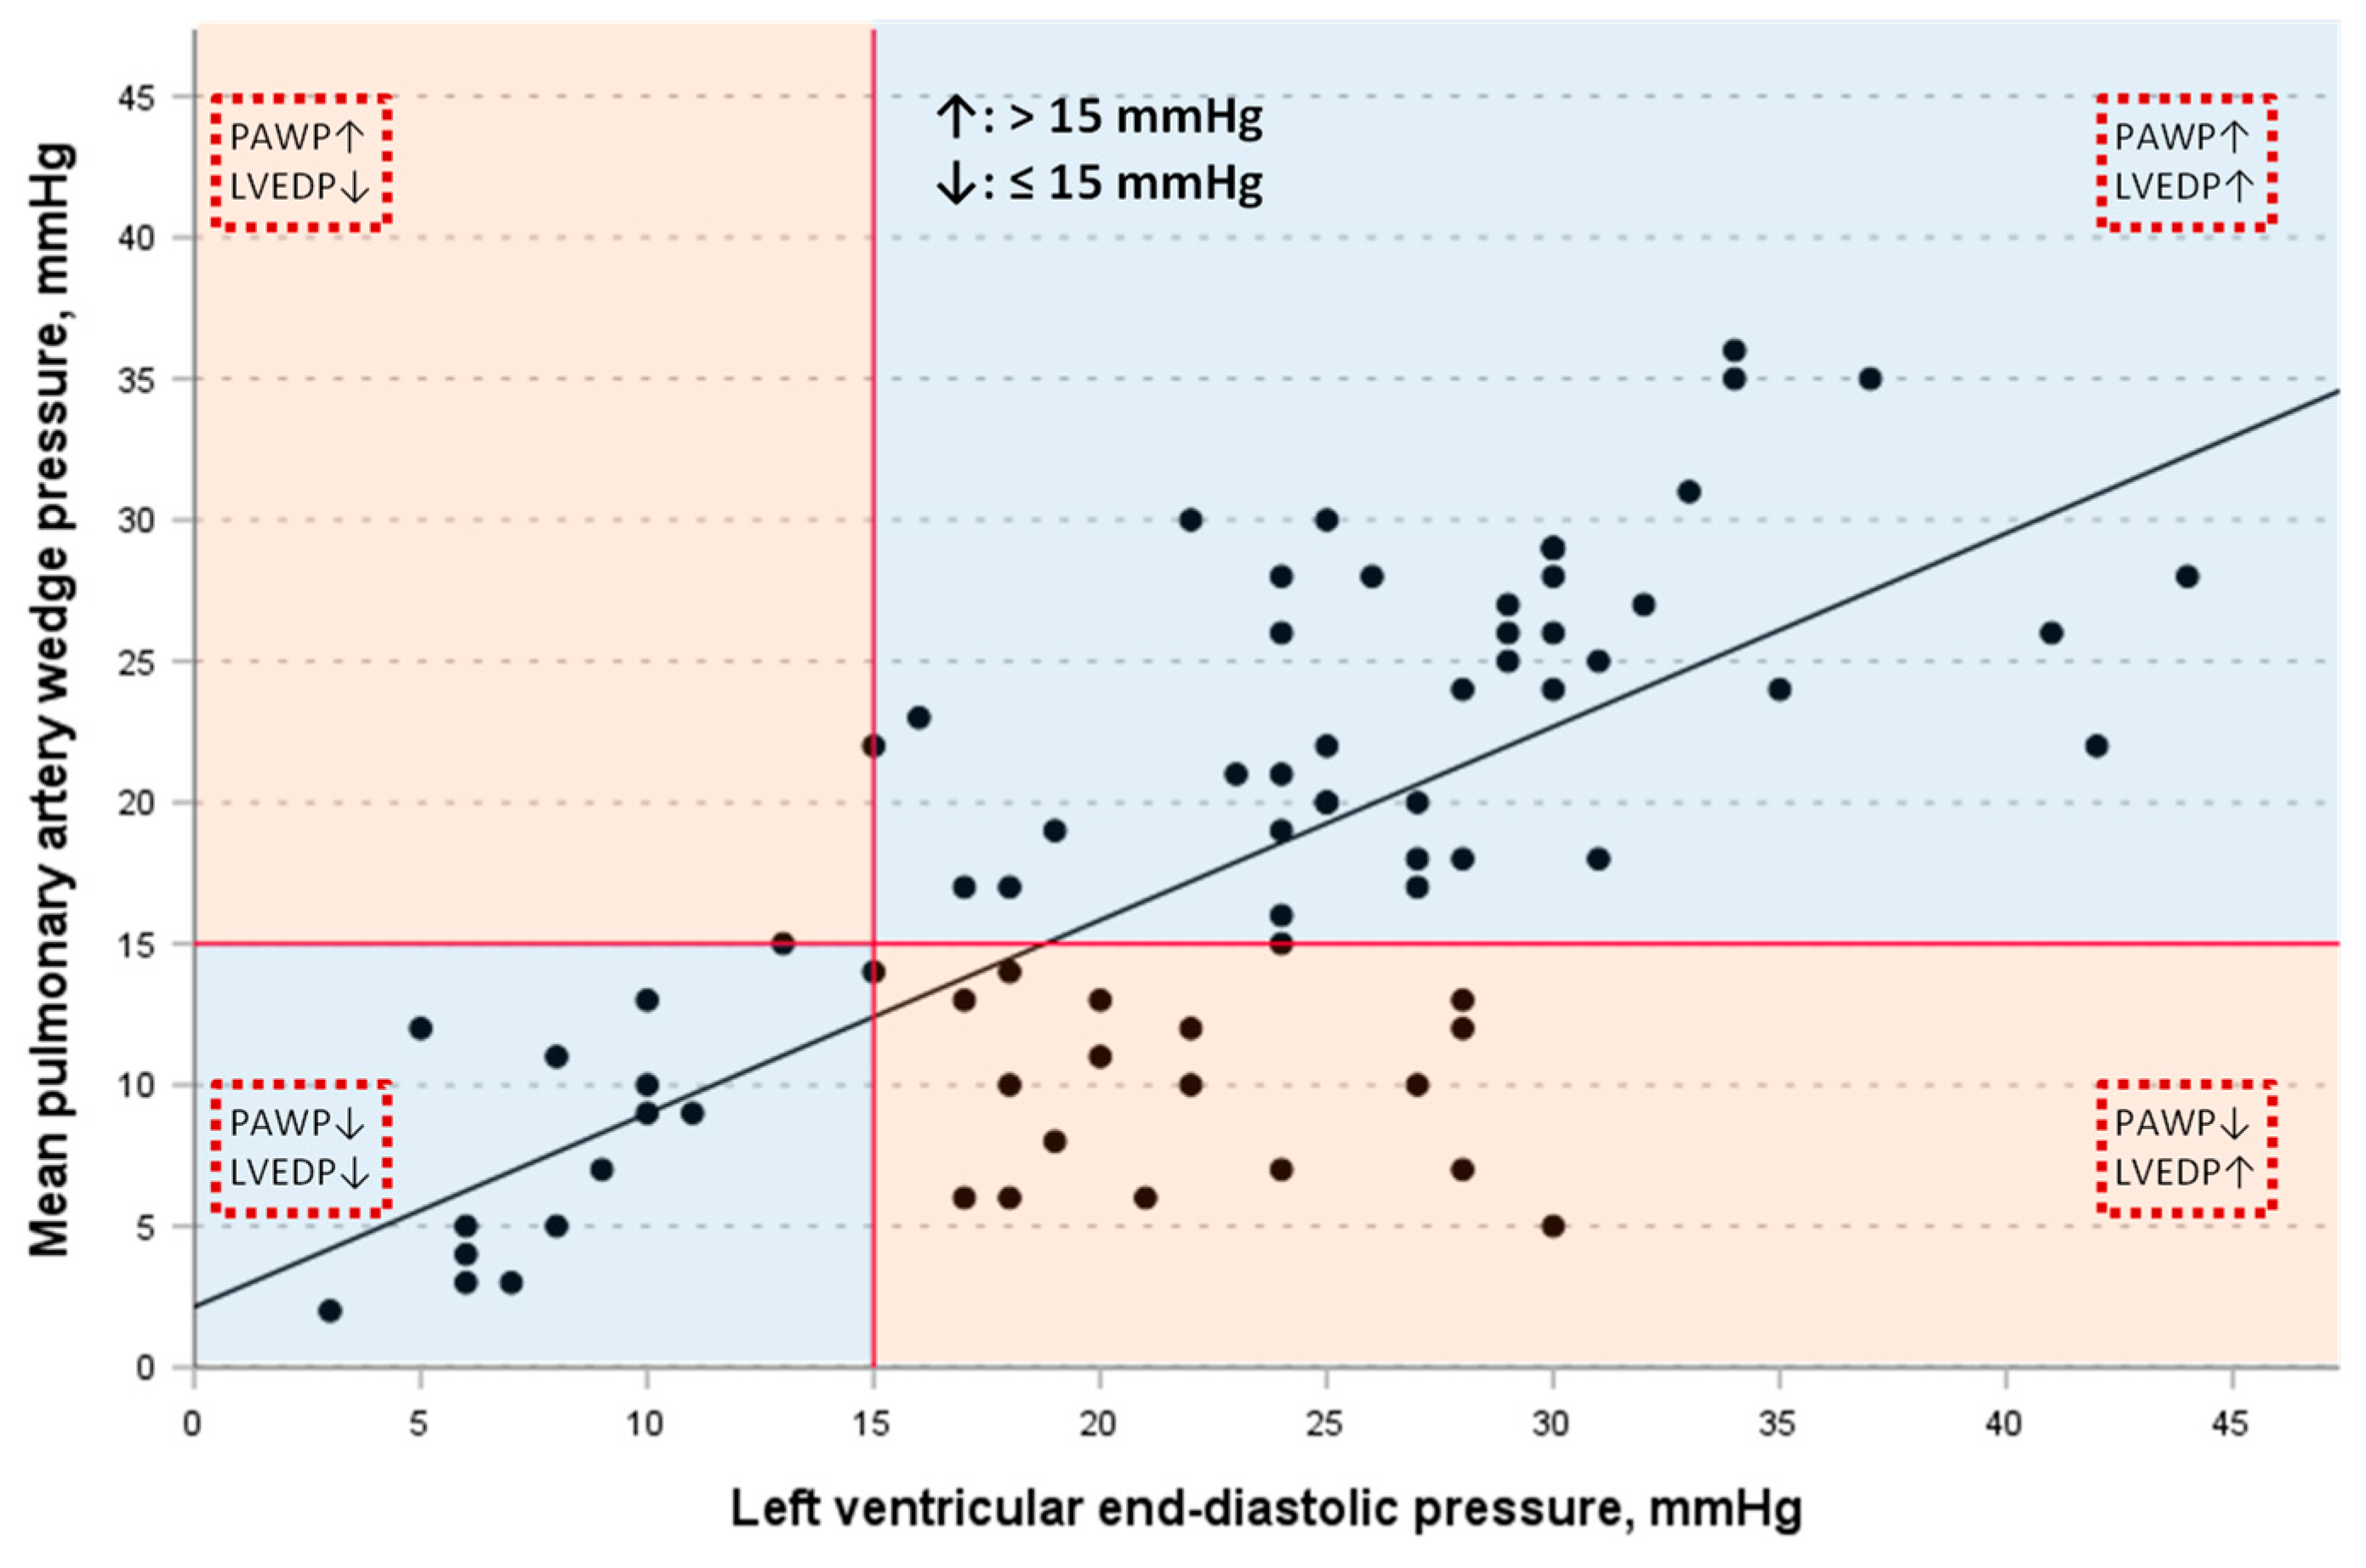

3.3. Correlation of PAWP with LVEDP

3.4. Linear Regression Models